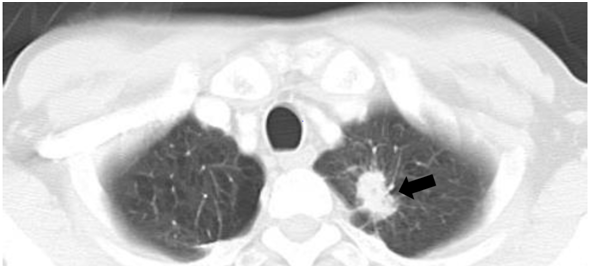

In 2015, a 62-year-old female presented to our hospital with gait disturbance and numbness in the bilateral lower extremities. There was a past history of adenocarcinoma in the apical portion of left lung that had been treated with chemotherapy and radiation in 2012 (Figure 1). In 2013, a brain metastatic tumor from lung cancer occurred that was treated with an operation and gamma knife.

Figure 1 Computed tomographic image of the chest. The tumor can be seen in the apex of the left lung (black arrow).